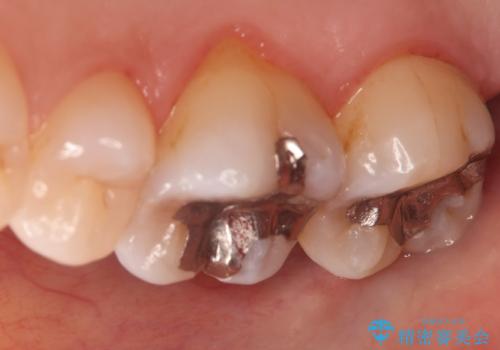

- 昔入れた金属の被せ物を白い物に変えたいと思い来院された患者様です。レントゲン等確認し審美的によく、強度のあるセラミックインレーにて治療いたしました。

審美的に良い補綴物に変わり満足いただきました。かみ合わせも問題なく快適に食事できているとのことでした。